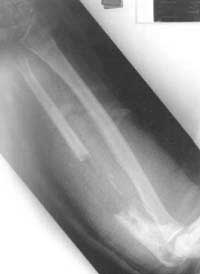

I bring the following case which is on-going and your thoughts would be of interest. 29yr old male left hand dominant Occupation: Chef six months ago presents initially with "night stick " with closed fracture to Left proximal ulnar shaft to hospital outside UK . This is treated with ORIF. This soon becomes infected and eventually the patient transfers back to United kingdom for an aggressive debridement (see films)

He is then put into an above elbow plaster and referred to our non union clinic. When seen now he is six months from initial injury unable to work and still wearing an above elbow POP . on exam out of POP: soft tissues fully healed no clinical infection no longer on antibiotics. wrist movements slight restricted but pain free pronation 10 degs supination 70 degrees elbow range 40 - 110 degrees pain free sensation normal Hand function normal except for Flexor pollicis longus not functioning 6 cm deficiency in ulna over to you for discussion.